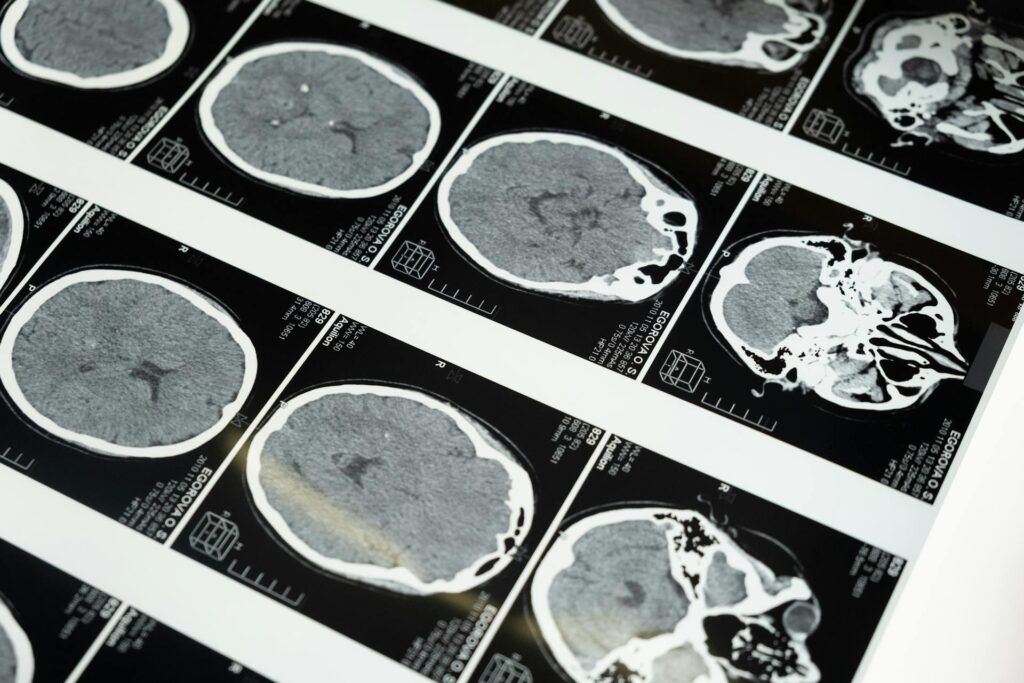

Απύρηνα σωμάτια στον εγκέφαλο που βρίσκονται μεταξύ ζωής και αδράνειας κινούνται αυτόβουλα, μεταφέροντας τοξικές πρωτεΐνες και φλεγμονώδεις παράγοντες σε υγιείς νευρώνες. Ονομάζονται zombosomes (σωμάτιο ζόμπι) και, παρά το όνομά τους που παραπέμπει σε επιστημονική φαντασία, είναι απόλυτα πραγματικές, και μέχρι τώρα άγνωστες, οντότητες που «αλωνίζουν» μέσα στον εγκέφαλο.

Μάλιστα, αυτά τα μικροσκοπικά σωμάτια μπορεί να είναι ένας σιωπηλός «ένοχος» για τη διάδοση της νόσου Πάρκινσον και πιθανώς και άλλων νευροεκφυλιστικών ασθενειών. Τα zombosomes περιγράφηκαν για πρώτη φορά, και μάλιστα πρόσφατα, από την ομάδα της Anna Erlandsson στο Πανεπιστήμιο της Ουψάλα, στη Σουηδία.

Επιπλέον, προκαλούν ένα φαινόμενο μετάδοσης της γήρανσης, ωθώντας και άλλα υγιή κύτταρα να υιοθετήσουν μια παρόμοια τοξική συμπεριφορά. Υπάρχουν υποψίες ότι εμπλέκονται σε νευροεκφυλιστικά νοσήματα, όπως η νόσος Αλτσχάιμερ ή η νόσος Πάρκινσον, καθώς και σε καταστάσεις χρόνιας νευροφλεγμονής».

Οι ερευνητές αναφέρουν στη νέα μελέτη πως στην Πάρκινσον, η α-συνουκλεΐνη, μια πρωτεΐνη που είναι ο βασικός μοριακός ύποπτος για τη νόσο και η οποία υπό φυσιολογικές συνθήκες συμμετέχει στη λειτουργία των συνάψεων, αρχίζει να διπλώνει λανθασμένα και να σχηματίζει τοξικά συσσωματώματα. Τα αστροκύτταρα «καταπίνουν» την πρωτεΐνη μεν, αλλά δεν καταφέρνουν να την αποικοδομήσουν πλήρως.

Οι ερευνητές έδειξαν ότι τα zombosomes μπορούν να «φιλοξενήσουν» παθολογικά συσσωματώματα της πρωτεΐνης α-συνουκλεΐνης, και μάλιστα, ένα μέρος αυτών των παθολογικών συσσωματωμάτων που συσκευάζεται μέσα στα zombosomes να «αποσταλεί» σε γειτονικά κύτταρα. Έτσι, η παθολογία μεταφέρεται από κύτταρο σε κύτταρο μέσα στον εγκεφαλικό ιστό.

Ακόμη πιο ανησυχητικό είναι ότι τα zombosomes φαίνεται να είναι εξαιρετικά αποτελεσματικά στη διάδοση της νόσου. Παρότι μεταφέρουν μικρότερη ποσότητα α-συνουκλεΐνης συγκριτικά με ολόκληρα κύτταρα, προκαλούν δυσανάλογα ισχυρή παθολογική απόκριση. Λειτουργούν σαν μικρά, ευέλικτα πακέτα υψηλής επικινδυνότητας που διεισδύουν βαθιά στον εγκεφαλικό ιστό και «σπέρνουν» την παθολογία σε περιοχές που διαφορετικά θα ήταν δύσκολο να προσβληθούν.

Κατά κάποιο τρόπο τα zombosomes λειτουργούν σαν “δούρειοι ίπποι”. Μεταφέρουν την παθολογική α-συνουκλεΐνη σε αστροκύτταρα, σε νευρώνες και ακόμη και σε τρισδιάστατα εγκεφαλικά οργανοειδή στο εργαστήριο, πυροδοτώντας νέα παθολογικά γεγονότα και ενισχύοντας τη συσσώρευση της πρωτεΐνης, που είναι ένα από τα χαρακτηριστικά “αποτυπώματα” της Πάρκινσον.

Το πιο σοκαριστικό είναι ότι παρόμοια σωμάτια που φέρουν παθολογικά τροποποιημένη α-συνουκλεΐνη εντοπίστηκαν και σε ανθρώπινους εγκεφάλους, τόσο σε ασθενείς με Πάρκινσον όσο και σε υγιείς. Αυτό δείχνει ότι δεν πρόκειται για μια ανωμαλία, αλλά για φυσιολογικό μηχανισμό επικοινωνίας των αστροκυττάρων, που όμως μπορεί να “χαλάσει” όταν ο εγκέφαλος χάνει την ισορροπία του. Το πρόβλημα δεν είναι τόσο η παρουσία των zombosomes, αλλά ότι μπορούν να μετατραπούν σε «κούριερ» τοξικού φορτίου.